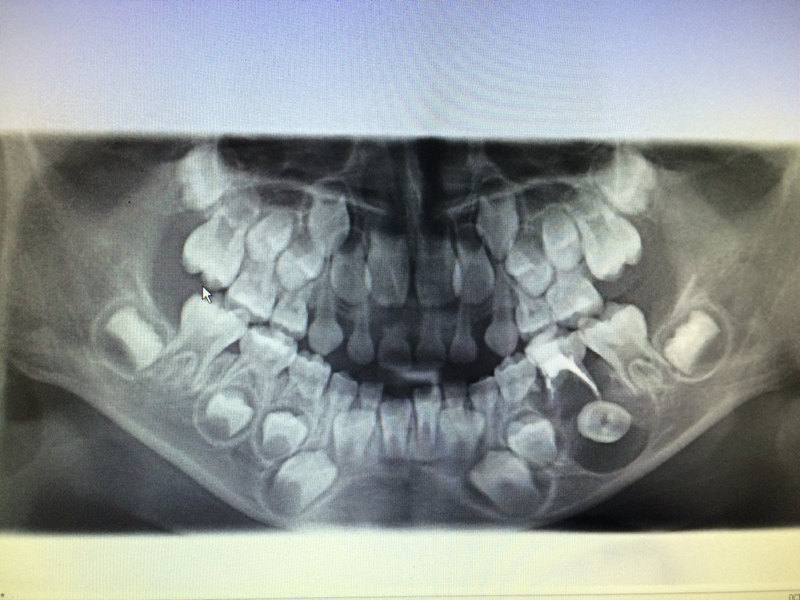

1.健康的乳牙才能咬碎食物,促進(jìn)消化,有助于兒童面部正常發(fā)育。 2.替下方新牙占位置,并誘導(dǎo)恒牙的正常萌出。 3.健康的乳牙列有助于兒童的正確發(fā)音。 4.健康完整的乳牙列有助于保護(hù)兒童積極向上的心理。 乳牙齲齒要補(bǔ)嗎? 不少人認(rèn)為乳牙反正要換,壞了不必治,那可就錯(cuò)了。乳前牙從5~6歲開始替換,而乳磨牙要到12~13歲才能換完,簡(jiǎn)而言之,換牙是個(gè)漫長(zhǎng)的過程。如果乳牙齲壞不治療,除了會(huì)造成我們上面講的那些危害,還會(huì)因?yàn)檠栏l(fā)炎而影響乳牙下方恒牙的發(fā)育,造成恒牙發(fā)育不良甚至發(fā)育停止;如果在正常換牙之前乳牙過早缺失,會(huì)出現(xiàn)恒牙長(zhǎng)出位置不足而造成排列不齊,影響孩子一生的口腔健康。所以,乳牙齲齒應(yīng)及時(shí)治療,省得“小洞不補(bǔ)大洞吃苦”。